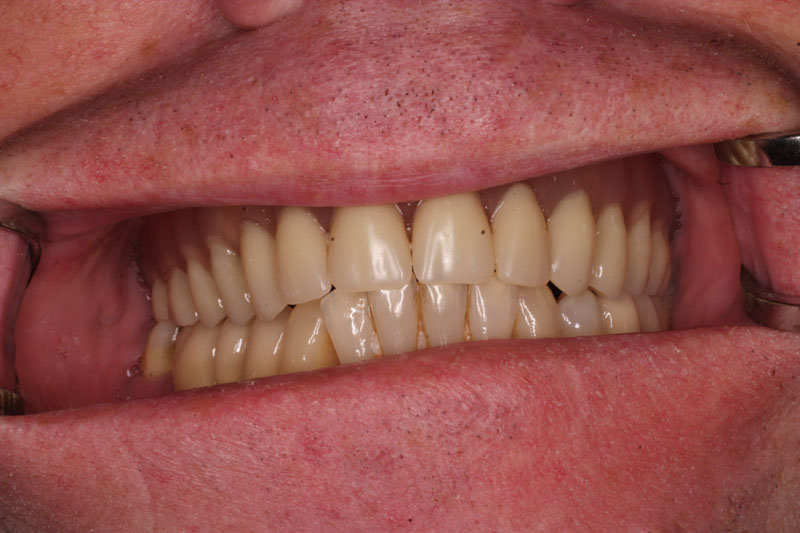

Bezzubá čelist je hlavní indikací pro ošetření pomocí implantátů. Zejména celkové zubní náhrady v dolní čelisti mají velice nízkou stabilitu a držení díky velkému úbytku kosti.

S pomocí zubních implantátů můžeme díky různým kotevním systémům (třmeny, kulové hlavy, Locatory) zajistit stabilitu a držení protézy nebo při použití většího počtu implantátů zhotovit pevné náhrady – můstky nalepené nebo našroubované na pevno na implantáty.

S těmito typy náhrad můžeme dosáhnout perfektní funkci, výbornou estetiku, fonetiku a současně zajistit u pacienta možnost dobré hygienickou péče a čištění, která je pro životnost implantátů velice důležitá.